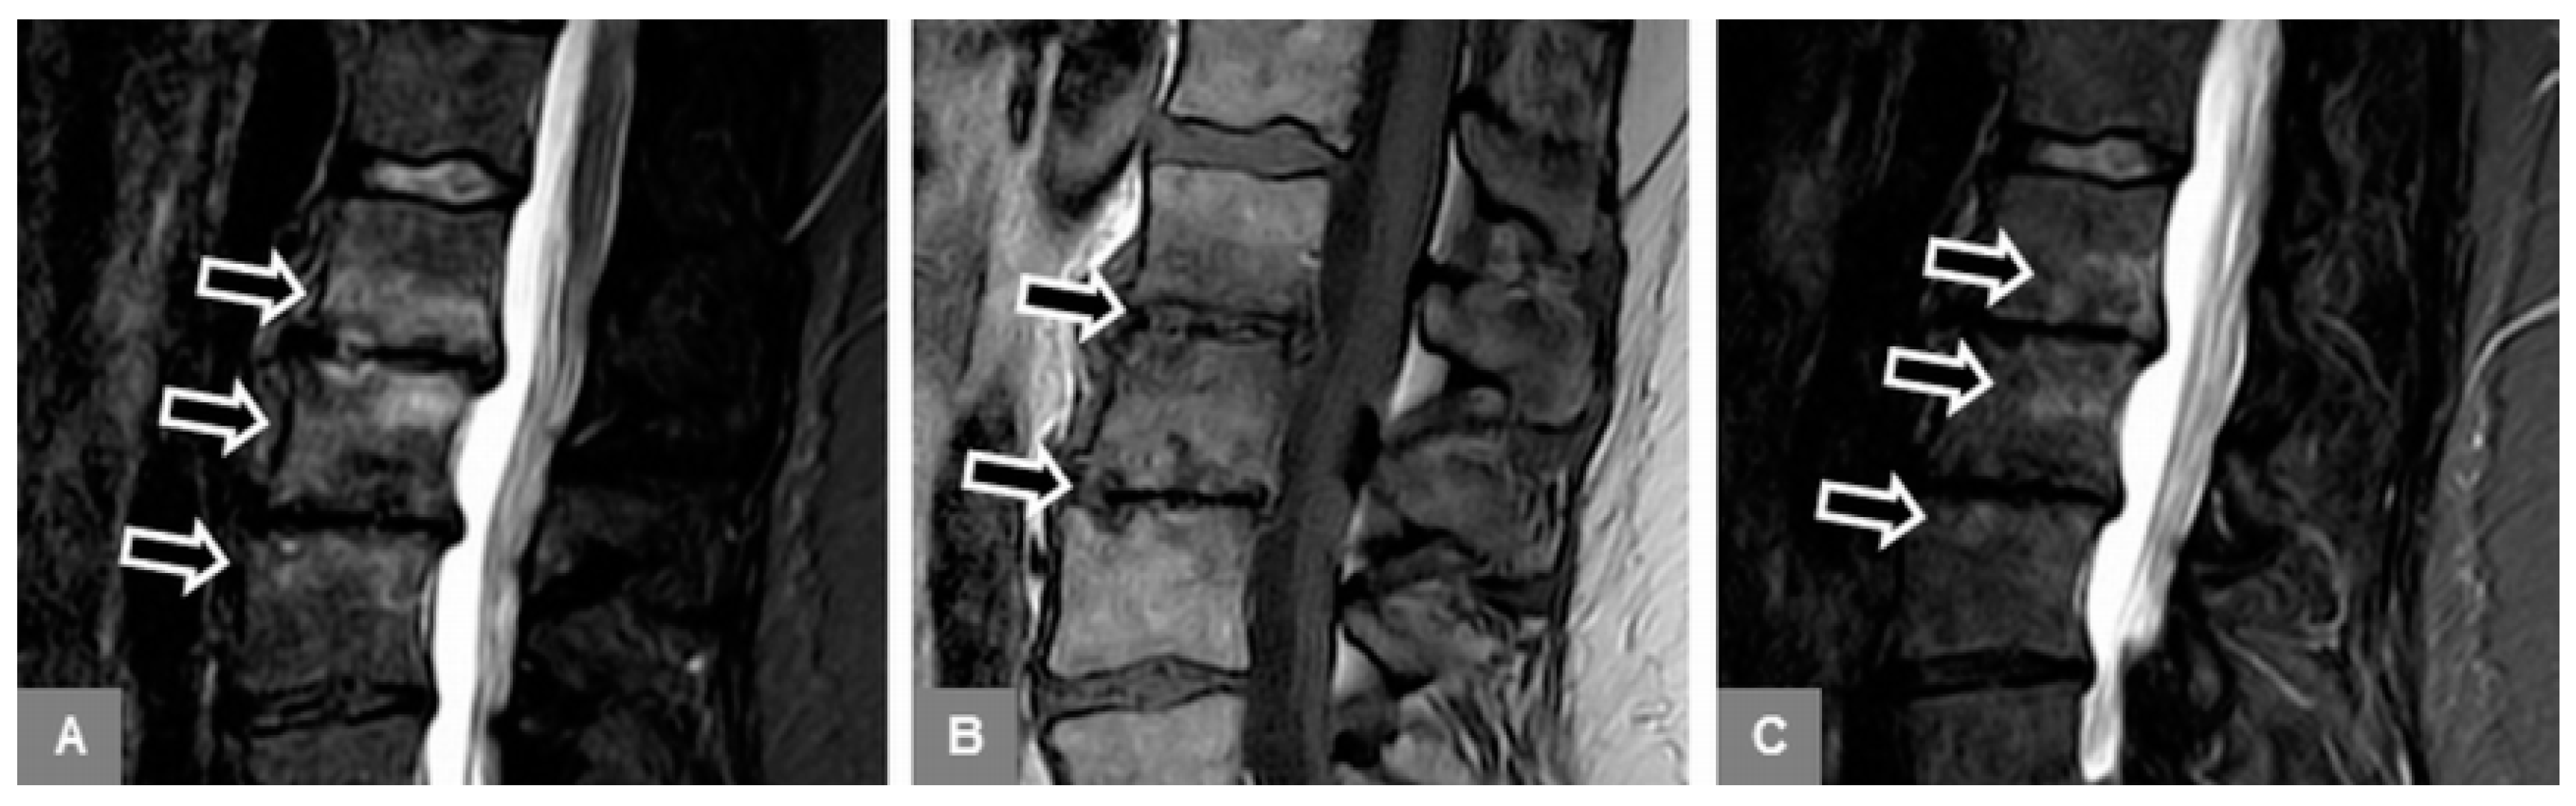

3.1. Bone Marrow Edema Extent, T1-w Signal Ratios of Edema to Unaffected Bone, and Visual T1-w Signal Assessment